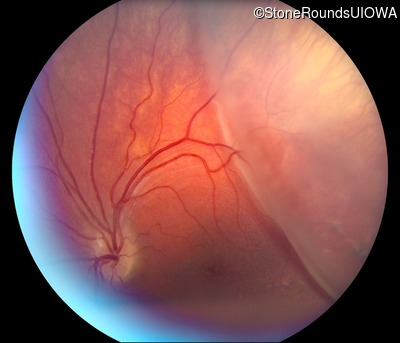

Visit at age: 14 years

Fundus Photography - Left - 20/70 +1

Exemplar